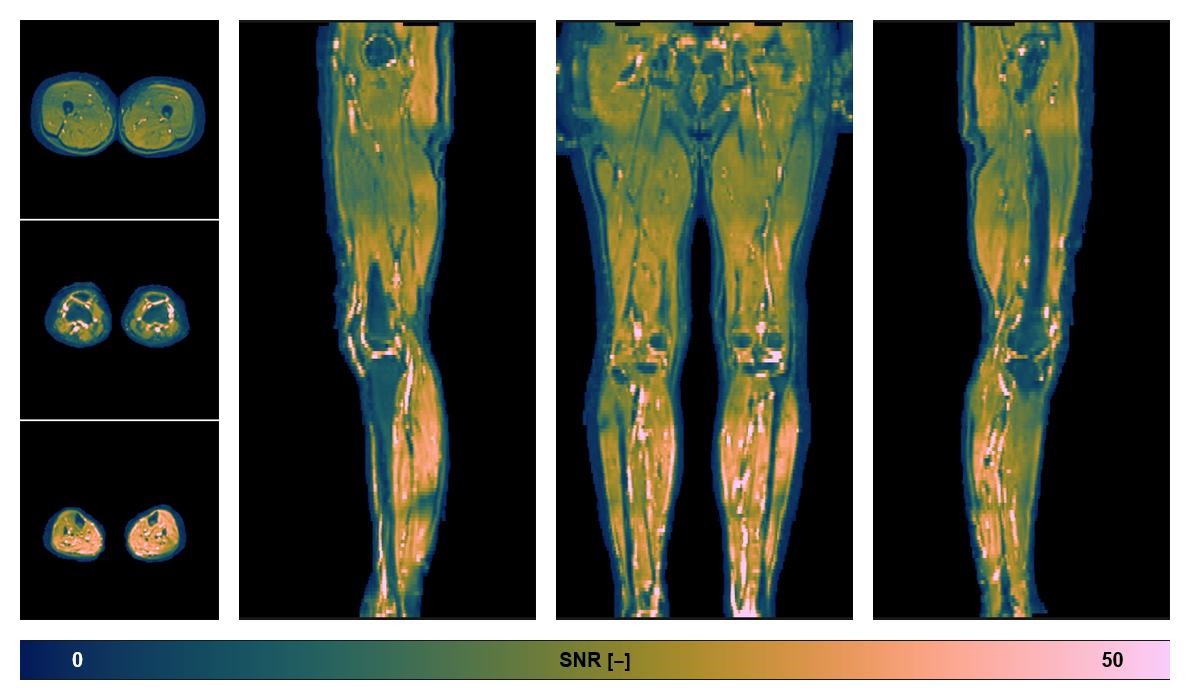

• SNR of the unweighted image

SNR distribution of the unweighted diffusion data.